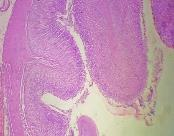

All the animals were observed daily for clinical signs of toxicity and morbidity. Individual animal body weights were recorded at receipt (on day 1) and weekly thereafter and at the time of sacrifice (fasting body weights). Histological examinations of various organs (brain, kidney, liver, small intestine and stomach) were carried out after 28 d using haematoxylin and eosin as staining agents. The organs were preserved in 10 % formalin solution.

On administration of TPSY, the animals in all groups were found to survive at the end of 28 d of study. The histological results are shown in table 4. Liver tissue showed minimal degeneration of hepatocytes compared to control at the highest dose of 350 mg which was however reported to be non-toxic.

Mild tubular degeneration was observed in kidneys Stomach tissue displayed moderate changes compared to control, with minimal degeneration of mucosal cellsat highest dose of 350 mg. Large intestine showed marked submucosal edema but the mucosal tissue appeared to be normal at the highest dose of 350 mg. No abnormality was observed in brain tissues at a low and medium dose. Mild submucosal edema was observed at 350 mg/kg. These results point to the negligible toxicity associated with the thiolated polymer and hence it can be considered to be safe for use as a pharmaceutical excipient.

Table 4: Histological results of repeated dose toxicity studies of TPSY (n=5)

| Organs | Normal saline | TPSY dose strength | ||

| Control | 70 mg/kg | 175 mg/kg | 350 mg/kg | |

| Liver | Normal architecture of liver, nothing abnormal detected. | Nothing abnormal detected. | Minimal degeneration of hepatocytes. | Minimal degeneration of hepatocyte and infiltration of inflammatory cells. |

| Kidney | Normal architecture of kidney, nothing abnormal detected. | Minimal tubular degeneration. | Mild tubular degeneration and congestion of blood vessels. | Mild tubular degeneration. |

| Stomach | Normal architecture of Stomach, Nothing abnormal detected. | Minimal degeneration of mucosal lining cells. | Mucosal cells were enlarged and were darkly stained. | Minimal degeneration of mucosal cells, accumulation of dark staining material in the gland. |

| Brain | Normal architecture of the brain, Nothing abnormal detected. | Nothing abnormal detected. | Nothing abnormal detected. | Minimal neuronal degeneration. |

| Large intestine | Papillary projections with goblet cells. | Mucosal lining no infiltration of inflammatory cells. | Minimal infiltration of inflammatory cells and congestion. | Marked submucosal edema, mucosal tissue appears normal. |

Fig. 8: Histology of various tissues at highest dose strength of 350 mg/kg body weight